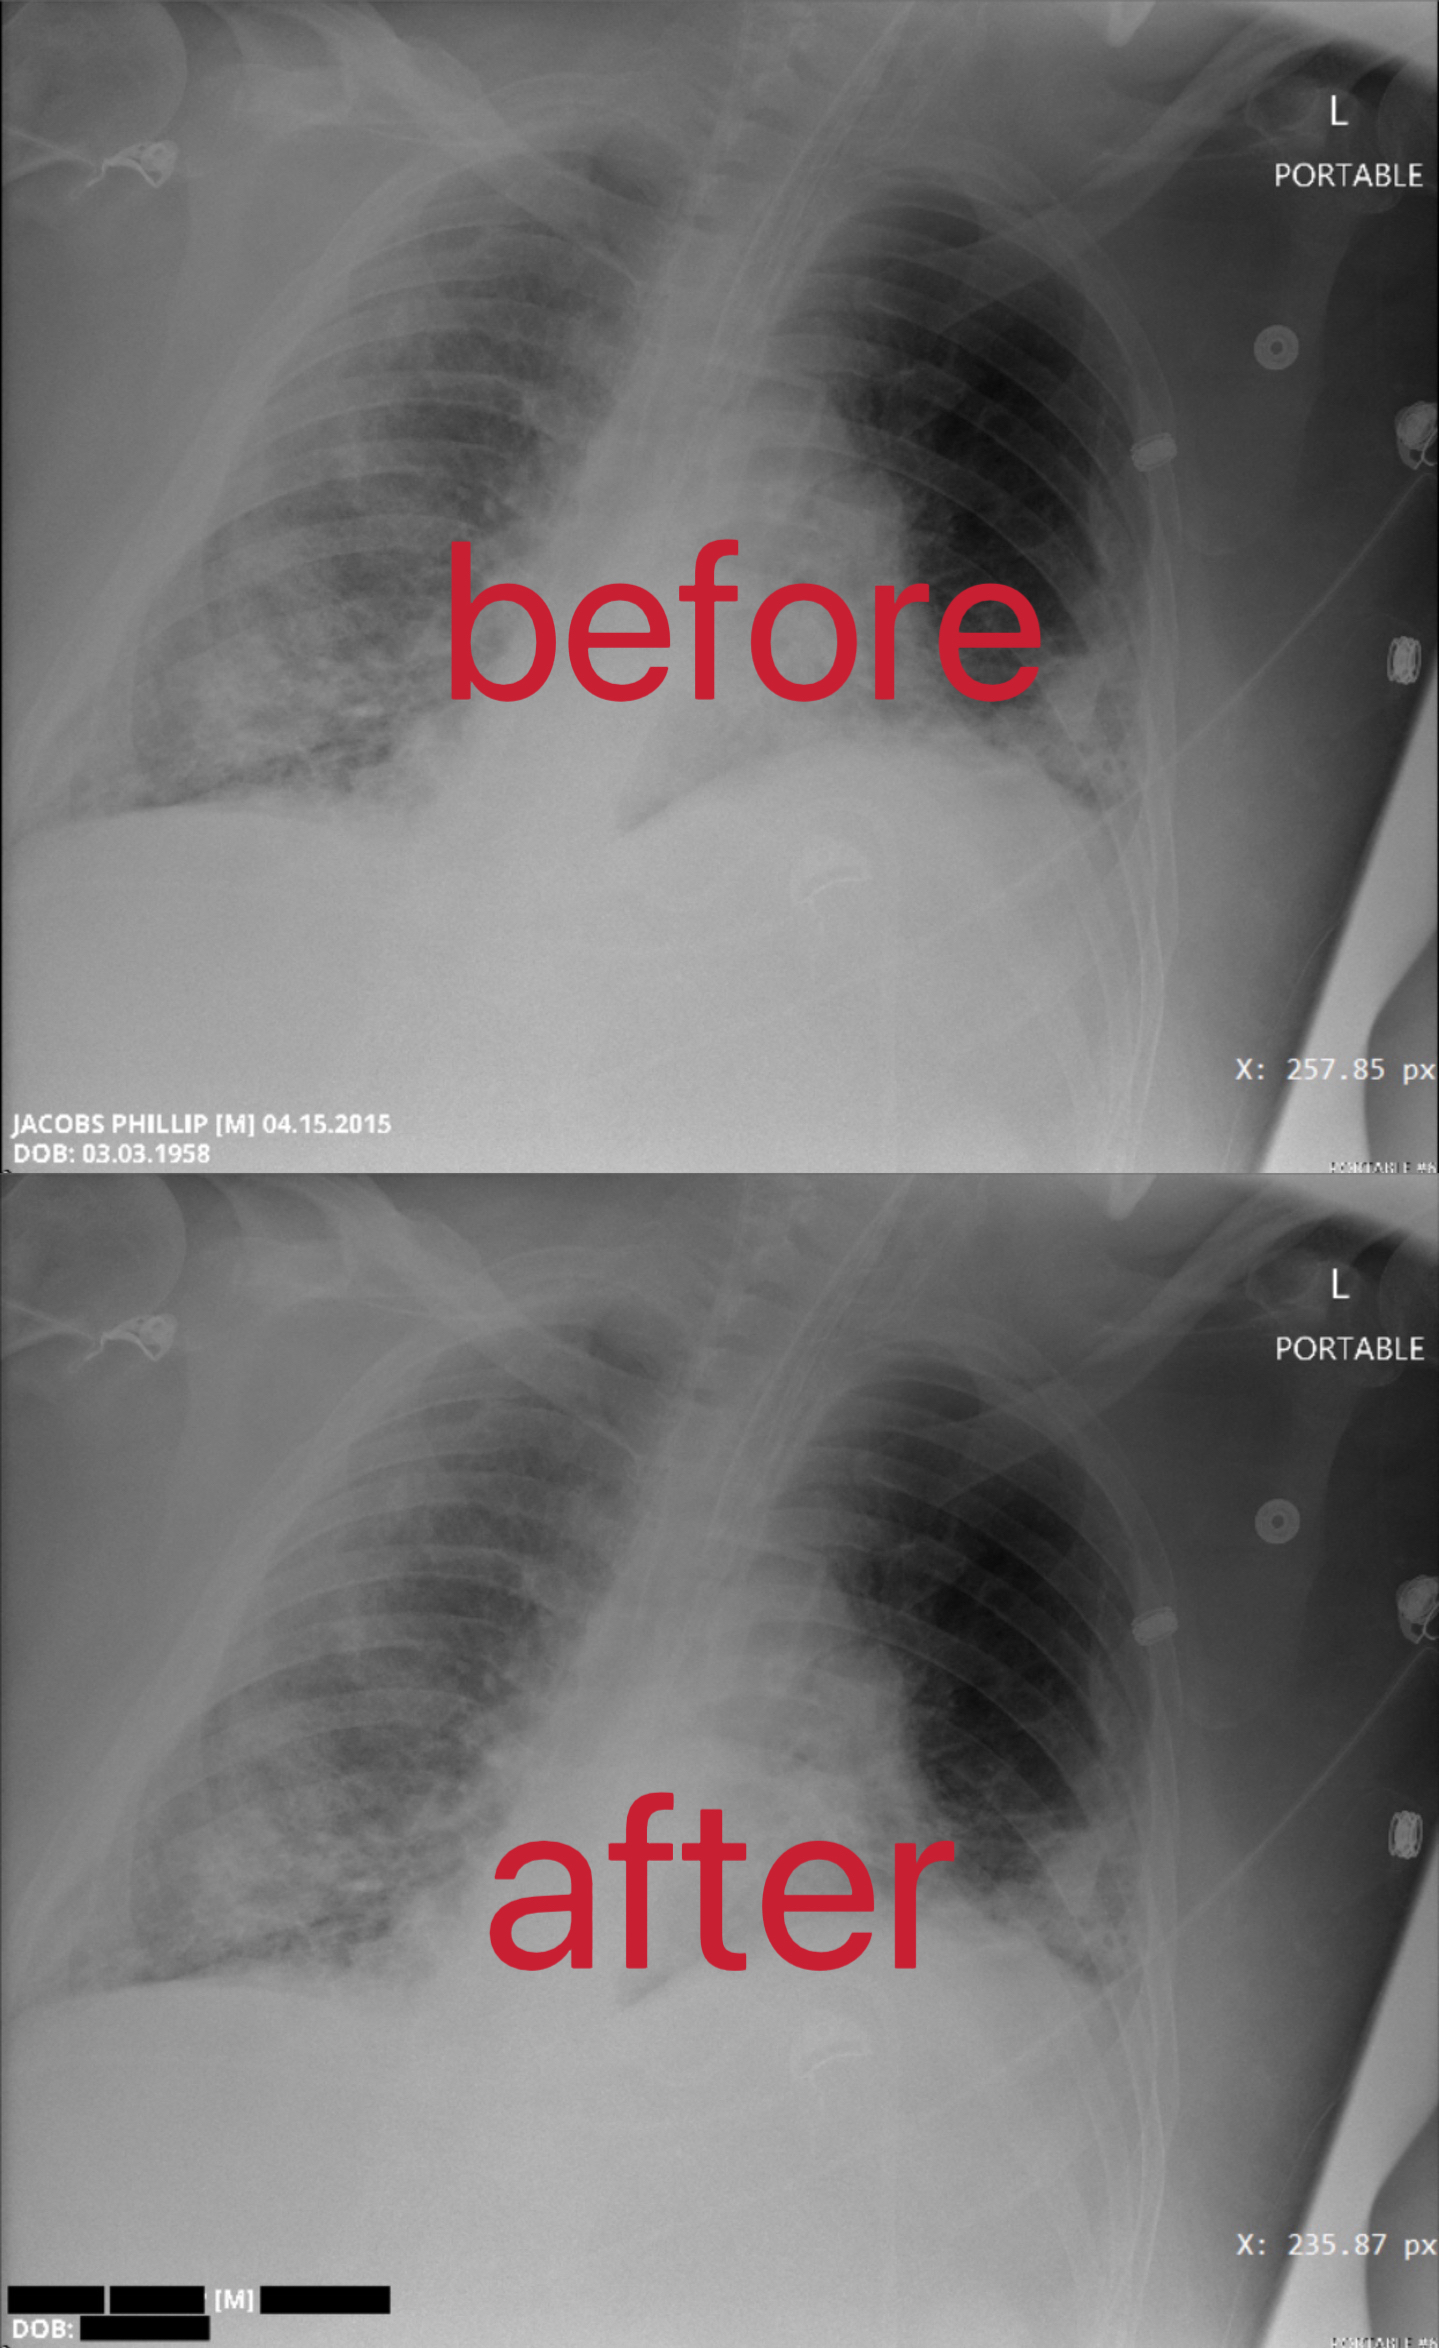

Examples of the final implementation of the pixels masking action is depicted in Figure 2, where the left of the figure represents the DICOM file before the action, and the right of the figure shows the DICOM file after the action. And another example is shown in Figure 3.

Figure 3: Another example of the final implementation of the pixel masking action.